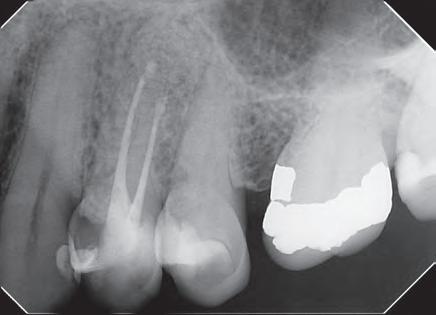

En la segunda sesión, 15 días después, realizamos la obturación convencional del tercio apical del canal con gutapercha, llenado de la cavidad reabsortiva con BIO-C ® REPAIR (Angelus, Londrina - Brasil) (Figura 7, 8 y 9), condensándolo contra las paredes con condensadores específicos y bolita de algodón humedecida y realizamos el sellado coronario con resina.

Figura 7 - BIO-C ® REPAIR (Angelus, Londrina - Brasil).

8 - Radiografia final

9 - Cavidad reabsortiva rellenada com BIO-C® REPAIR